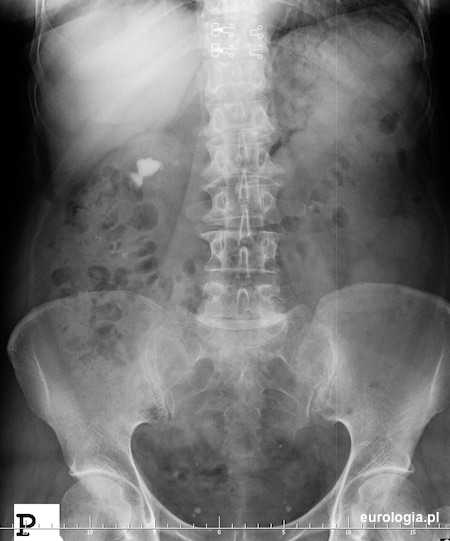

Urografia - kamica odlewowa nerki prawej oraz drobny złóg w połaczeniu miedniczkowo-moczowodowym nerki lewej

Cień wapienny mogący być złogiem odlewowym widoczny w rzucie prawego pola nerkowego. Kilka drobnych flebolitów w miednicy małej.